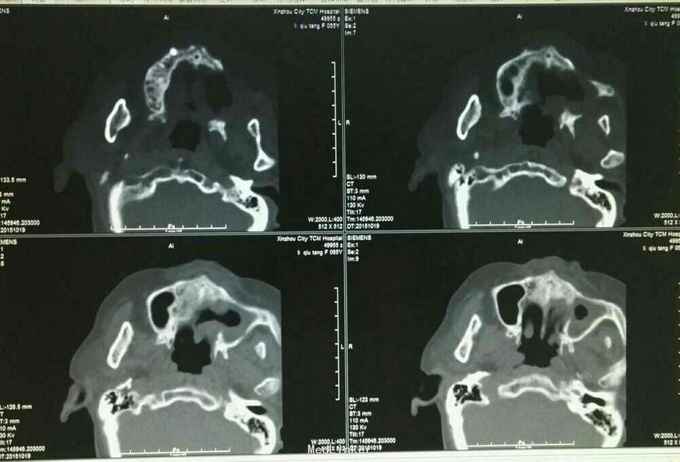

主诉:左上牙龈癌术后2月半余 病史:患者,女65岁,详见图:

查体、辅助检查见图:

诊断:左上牙龈癌术后复发 治疗:2015.10.21CT引导下行碘125粒子植入术,图为术前定位